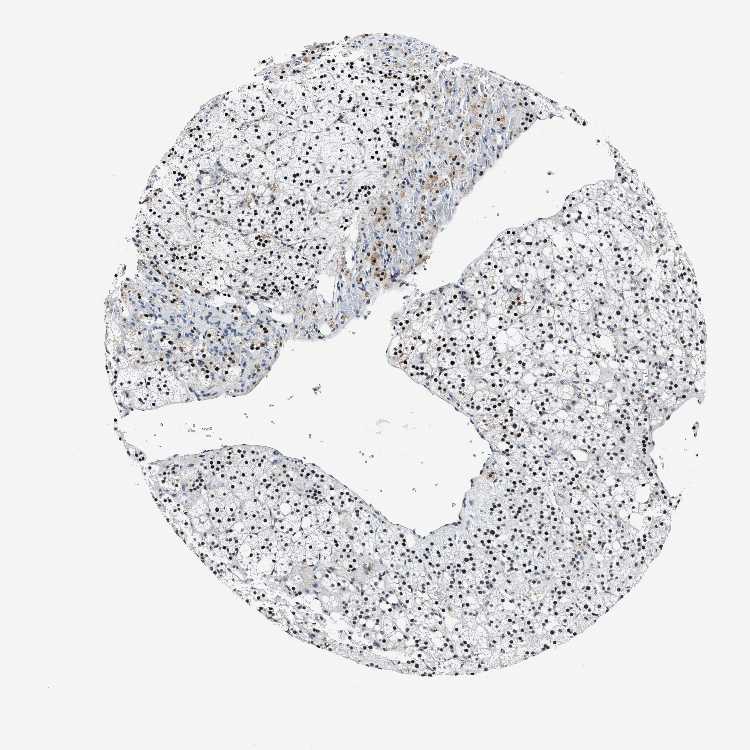

ADRENAL GLAND - Antibody stainingi

Antibody staining in the annotated cell types in the current human tissue is reported as not detected, low, medium, or high, based on conventional immunohistochemistry profiling in selected tissues. This score is based on the combination of the staining intensity and fraction of stained cells.

Each image is clickable and will lead to virtual microscopy that enables deeper exploration of all samples and also displays staining intensity scores, fraction scores and subcellular localization as well as patient and tissue information for each sample.

Antibody HPA020131

Glandular cells High